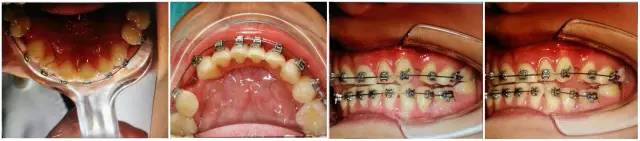

以上群里多位醫(yī)生的探討基本與權(quán)老師的處理方案接近。權(quán)老師的最終治療是通過樹脂暫時(shí)恢復(fù)尖牙引導(dǎo)功能,側(cè)方引導(dǎo),使上下前牙分離了,緩解前牙創(chuàng)傷;做完舌側(cè)的功能恢復(fù),后牙打開較多,在某種程度上對(duì)后牙也有很大保護(hù)。

(以下為治療后的照片:患者癥狀得到了良好改善。)

足以看出,尖牙保護(hù)(牙合)在臨床工作中的重要作用,它是以尖牙為支撐,對(duì)其他牙齒起到保護(hù)作用。其特點(diǎn)是正中關(guān)系(牙合)與正中(牙合)協(xié)調(diào);側(cè)方咬合運(yùn)動(dòng)時(shí),工作側(cè)只有尖牙保持接觸非工作側(cè)牙齒不接觸;在作前伸咬合運(yùn)動(dòng)時(shí),上下頜前牙切緣相對(duì)接觸,后牙不接觸。尖牙具有適合制導(dǎo)的舌面形態(tài),可使用(牙合)力趨于軸向;牙根長(zhǎng)且粗大,支持力強(qiáng);尖牙位居牙弓前部,在咀嚼時(shí)構(gòu)成第Ⅲ類杠桿,能抵御較大的咀嚼力;以及尖牙牙周膜感受器豐富,對(duì)刺激敏感,能及時(shí)調(diào)整反應(yīng)都是尖牙的有利條件。尖牙形態(tài)的恢復(fù)在此例正畸治療中,對(duì)前牙、后牙都起到了很好的保護(hù)作用,也能保證后期按照標(biāo)準(zhǔn)(牙合)進(jìn)行(牙合)重建時(shí)后牙無干擾。功能在先,美觀在后,權(quán)老師為您展示了這樣的治療理念。